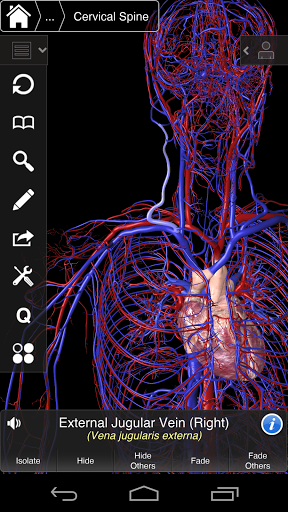

Основна анатомія 3 - це найновіша технологія та новаторський дизайн. Ріжучий 3D-графічний движок, зроблений на замовлення 3D4Medical з усього світу, наділений високоінформативною анатомічною моделлю і забезпечує високу якість графіки, яку не може досягти ніхто інший конкурент.

Програма являє собою унікальний підхід до вивчення загальної анатомії. Графіка не має аналогів і навчається, використовуючи інформативний контент та інноваційні функції, багатий та захоплюючий досвід.

⁃Винис

⁃ Артерії

НОВІ 3D-ТЕХНОЛОГІЇ

Основна Анатомія 3 чутлива, візуально приголомшлива і легка. Додаток повністю 3D, що означає, що ви можете переглядати будь-яку анатомічну структуру окремо, а також з будь-якого кута.

---- Більше 4000 дуже детальних анатомічних структур

---- Латинська номенклатура для кожної анатомічної структури